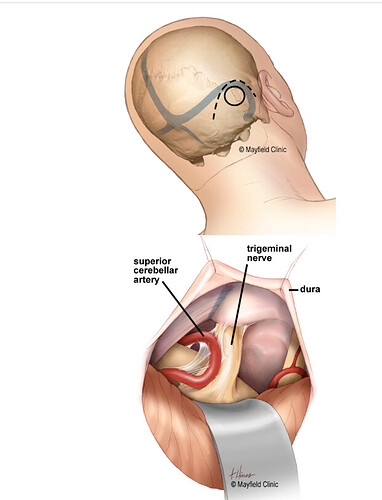

Looking in the internet to see how this MVD surgery is done, I am astonished to find how close the incision is to the transverse & Sigmoid sinuses (see below images from the internet).

Source : Microvascular Decompression (MVD) - Facial Pain Association